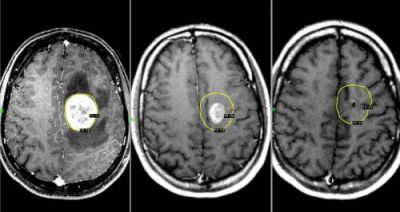

Рак мозга

При онкологическом заболевании мозга, у человека далеко не всегда болит голова. Но если такой симптом даёт о себе знать, болезнь протекает очень тяжело.

Головная боль, спровоцированная опухолью мозга, возникает по причине повышения внутричерепного давления. Чем быстрее растёт опухоль, тем сильнее повышается давление.

Возникает такой дискомфорт, преимущественно, утром. Практически всегда он сопровождается рвотой.

По мере прогрессирования заболевания, частота болевых приступов увеличивается, а дискомфорт становится сильнее.

Это приводит к тому, что больной быстро теряет вес, у него появляются судороги. При наличии симптомов рака мозга, следует незамедлительно обратиться к онкологу.

Если вовремя диагностировать заболевание, у больного есть все шансы на выздоровление. Однако если рак будет диагностирован на поздней стадии, шансы на успешное удаление злокачественной опухоли очень малы.

Опухоли мозга

Злокачественные опухоли характеризуются быстрым прорастанием в другие ткани с их последующей трансформацией. При этом метастазы могут наблюдаться сразу в нескольких участках мозга.

Такие опухоли плохо лечатся, а на поздних стадиях их развития спасти человека практически невозможно.

Клиническая картина

Характер болевых ощущений — постоянный, по мере развития заболевания продолжительность приступов увеличивается. Когда человек двигается, болевые ощущения усиливаются. Сначала они локализуются в области опухоли, потом, по мере увеличения внутричерепного давления, переходят в лобную и затылочную часть. Наиболее сильный дискомфорт наблюдается в ночное и утреннее время из-за скопления жидкости. Вены не справляются с оттоком крови, поэтому к болям прибавляются отёчность и застои. Боли давящие, распирающие, пульсирующие.

К головным болям затем добавляется рвота. При физической нагрузке или кашле болевые ощущения усиливаются, появляется двоение в глазах, временами исчезает зрение. Голова кружится, у пациента нарушается координация движений. Могут неметь конечности, ослабляется тонус мышц.

Иногда бывают эпилептические припадки, путается сознание.

Вмешательство врача

Необходима помощь терапевта, нейрохирурга, онколога, онколога-радиолога.

Диагностирование

Для диагностики используется МРТ мозга, ПЭТ, КТ мозга, ангиография и другие методы.

Лечение

- Для облегчения боли на ранних стадиях заболевания врачи рекомендуют мочегонные препараты и кортикостероиды, с помощью которых удаётся добиться частичного снятия отёка и нормализации кровоснабжения на поражённом участке.

- Удаление опухоли с помощью лазера, эндоскопии и ультразвука.

- Иссечение опухоли. Метод травматичен. Способы иссечения: трепанация черепа или удаление костных фрагментов.